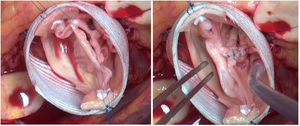

La laxitud y fragilidad de los tejidos hace que haya que prestar especial atención a algunos detalles técnicos durante la cirugía de preservación valvular aórtica en estos pacientes. En nuestra experiencia, para el reimplante usamos puntos de Ti-Cron 2/0 apoyados en teflón en el plano subvalvular. El uso del teflón sirve para evitar el desgarro de los tejidos. Asimismo, hay que recordar que el objeto de estas suturas es sujetar la prótesis al anillo dándole estabilidad, por lo que se debe anudar suavemente. En la porción membranosa del septo, el punto del anillo se da sin teflón y un poco más alto, para evitar dañar el velo y el sistema de conducción (figuras 3 y 4).

Inserción de los puntos de anillo en una válvula aórtica tricúspide en un paciente con síndrome de Marfan.

Se muestra en la imagen el anillo de una válvula aórtica tricúspide en un paciente con síndrome de Marfan. Marcamos con dermográfico la zona correspondiente al septo interventricular donde hay mayor riesgo de daño al tejido de conducción. Se observa cómo el punto de anillo a ese nivel se realiza más cerca de la comisura y sin parche.